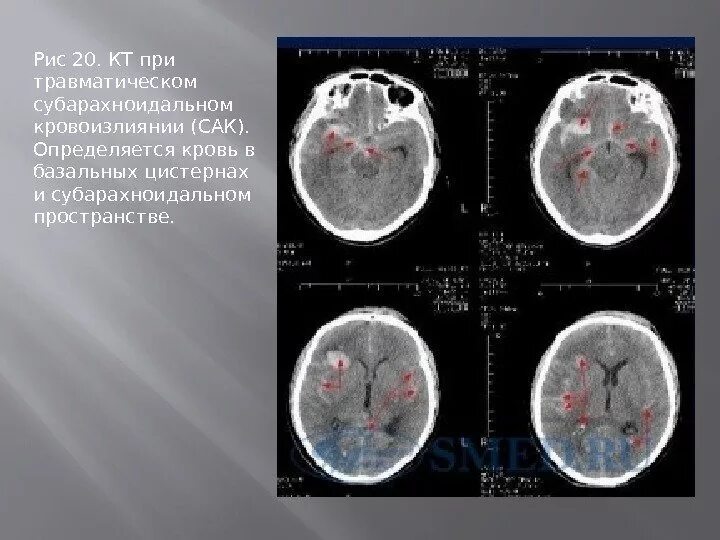

Цистерны на кт